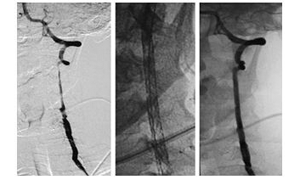

Վերոհիշյալ 3 հիվանդները, որոնց կոնսերվատիվ բուժումը եղել է ապարդյուն, ենթարկվել են վիրահատական բուժման: վիրահատական միջամտություններից երկուսը կատարվել են ներանոթային եղանակով, իսկ մեկը՝ բաց վիրահատական եղանակով: Ներանոթային վիրահատության ենթարկված երկու հիվանդներից մեկի մոտ առկա է եղել դոմինանտ ողնաշարային զարկերակի V2 սեգմենտի տարածուն շերտազատում: Կատարվել է ողնաշարային զարկերակի ստենտավորում Enterpirse նիտինոլային ստենտի միջոցով, որի օգնությամբ հաջողվել է վերականգնել ողնաշարային զարկերակի անցանելիությունը (նկար 1):Հետվիրահատական շրջանում 27 ամիս տևողությամբ դինամիկ հսկողության ընթացքում հիվանդի մոտ ուղեղի արյան շրջանառության կրկնակի խանգարումներ և հեմոռագիկ բարդություններ չեն դիտվել: Երկրորդ հիվանդի մոտ առկա է եղել ձախ ողնաշարային զարկերակի V3 սեգմենտի կեղծ անևրիզմա: Հիվանդի մոտ վնասվածքից 3 ամիս անց նկատվել են անցողիկ իշեմիկ գրոհի էպիզոդներ: Վերջիններիս կապակցությամբ հիվանդին նշանակվել է հակաագրեգացիոն թերապիա (Ասպիրին 325մգ/օր), որը սակայն եղել է ապարդյուն: Ուստի որոշում է կայացվել կատարել վիրահատություն՝ կեղծ

անևրիզմայի էնդովասկուլյար օբլիտերացիա միկրոպարույրներով: Հետվիրահատական շրջանը ընթացել է առանց բարդությունների:

Նկար 1. Ձախ ողնաշարային զարկերակի տարածուն շերտազատում, որը հաջողությամμ բուժվել է ներանոթային ստենտավորման միջոցով